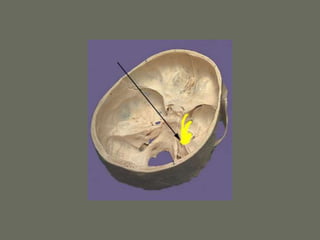

Tentorium and Falx

Tentorium